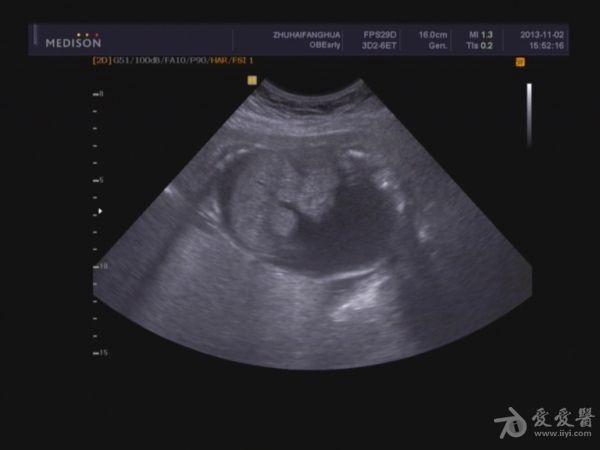

单胎妊娠;臀位,颅骨环基本完整,脑中线居中,CER: 24mm,CM:不清,双侧丘脑可见,侧脑室未见明显扩张,小脑可显示欠清,胎儿颈项部欠清,胎儿颜面显示不清,胸腔增大内见积液,腹壁完整,肝、可见,腹腔内大量积液,最大径约:71mm,胸腔内积液最大径:11.4mm,胃及膀胱显示不清。双肾显示不清。双侧四肢长骨显示欠清。

2.胎儿畸形,胸、腹腔大量积液,

因为羊水少,很多部位观察不清,四维图片基本没意义。期待几天后引产看结果。